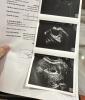

Как я долго ждала этих полосок🥹

Я беременна, для меня это просто невероятное ЧУДО!